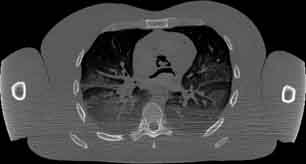

Visible Human male: Sectio transversalis 1422

CT

NMR

Pd                          / T2 \                         T1